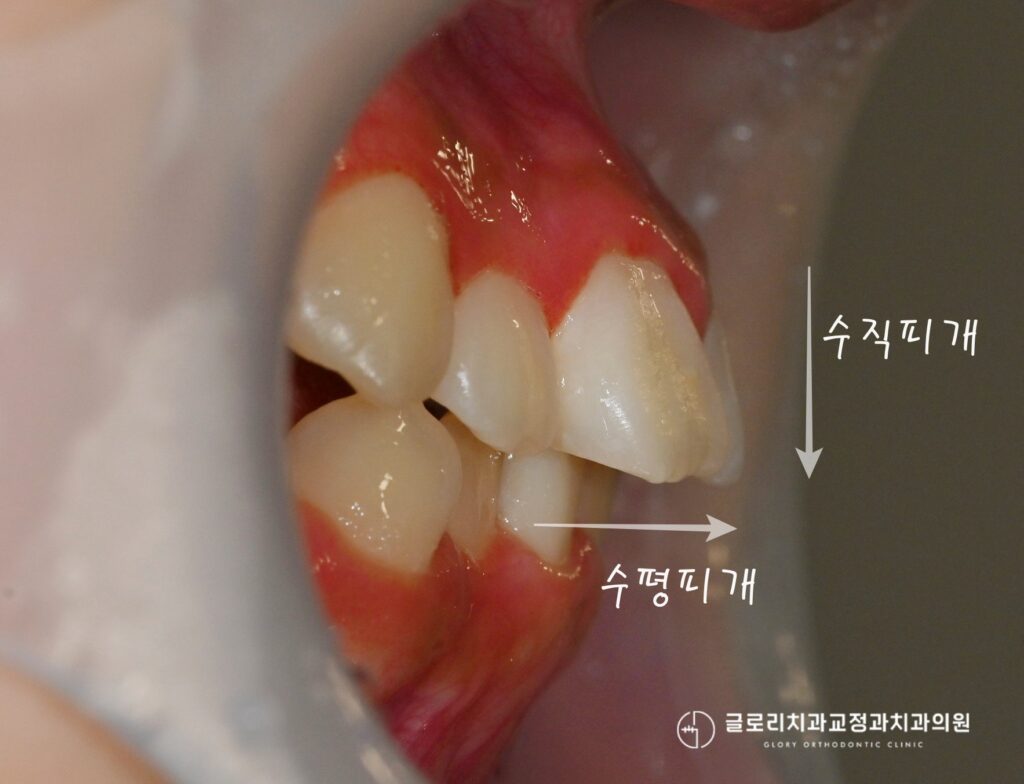

중랑구 교정치과 에서 구강사진을 보면 현재 위아래 이가 삐뚤하게 배열되어있으며 전치부 총생이 관찰됩니다.

또한 현재 과도한 수직, 수평피개의 양상도 보여집니다.

중랑구 교정치과 에서 설명드리길 이는 윗니가 아랫니를 덮는 정도와

앞뒤 거리가 과도한 것을 말하는데 이로 인해 돌출입의 모습을 띠고 있습니다.